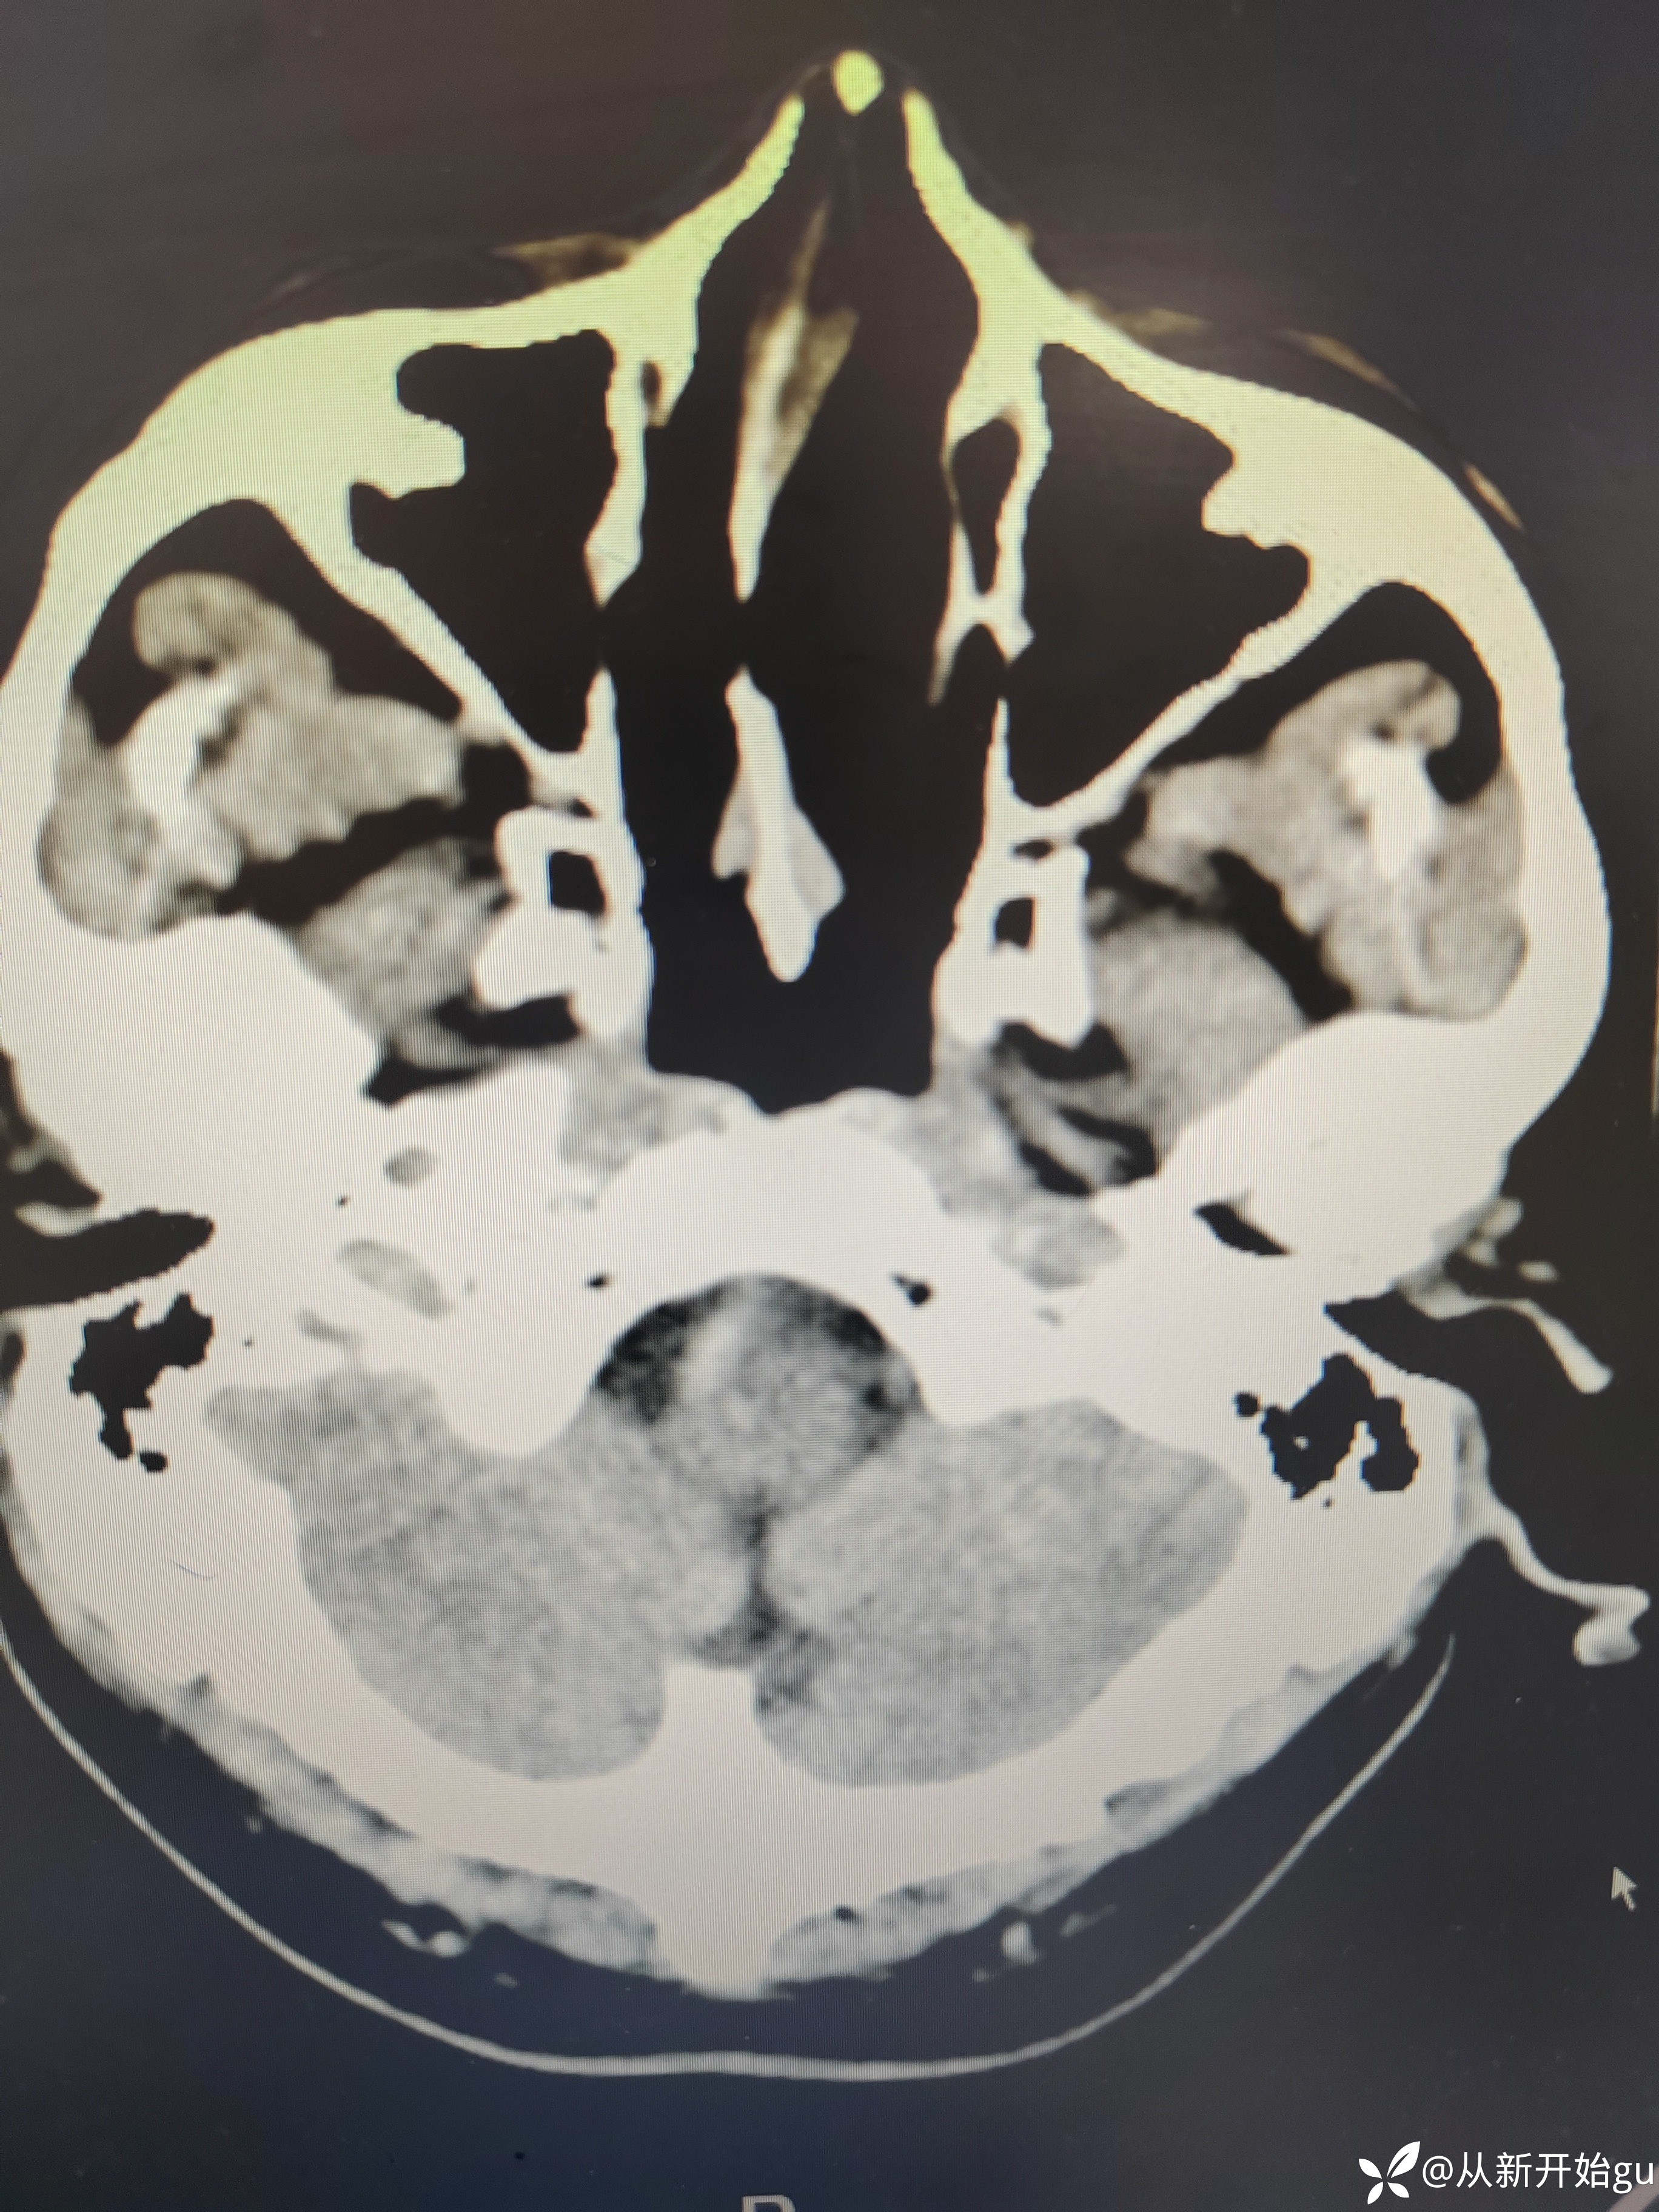

【检查】:完善颅脑CT.

【检查】:完善颅脑CT.